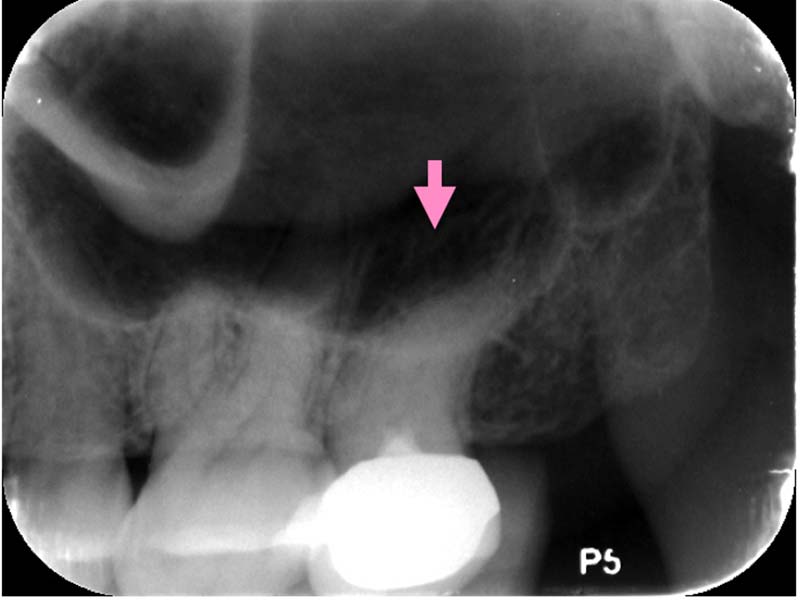

圖例為案例分享:

深度填補過後,持續冷熱敏感

依照症狀及顯微鏡下觀察,移除部分牙隨組織

術後三年追蹤檢查,狀況良好